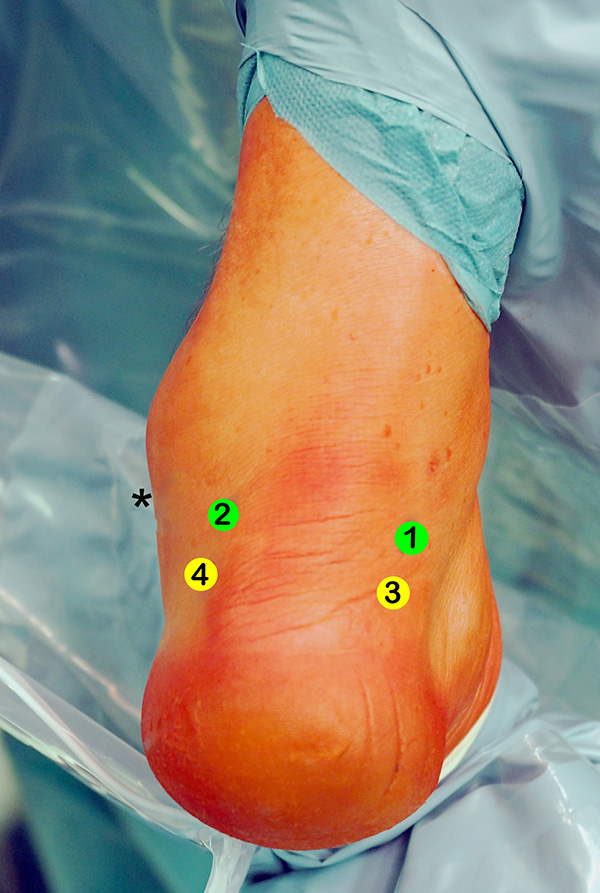

Abbildung 3

Übersicht der Arthroskopiezugänge für den arthroskopischen FHL-Transfer.

1 = posteromediales Portal.

2 = posterolaterales Portal.

3 und 4 = tiefe paraachilläre Portale.

Die hohen paraachillären Zugänge befinden sich auf Höhe der Außenknöchelspitze (*) unmittelbar medial und lateral der Achillessehne. Um den N. suralis nicht zu verletzen, wird die Haut nur vorsichtig inzidiert und die Weichteile werden mit einem Klemmchen aufgespreizt.

Gelegentlich kann intraoperativ die Anlage tiefer paraachillärer Zugänge erforderlich sein, um den Tuber calcanei adäquat darstellen zu können (siehe auch Kapitel „Endoskopische Therapie der Haglunddeformität“, Abbildungen 2-4).

Zum Lesen der Bildbeschreibung und zur Vollansicht bitte das Bild anklicken. Foto: M. Galla.